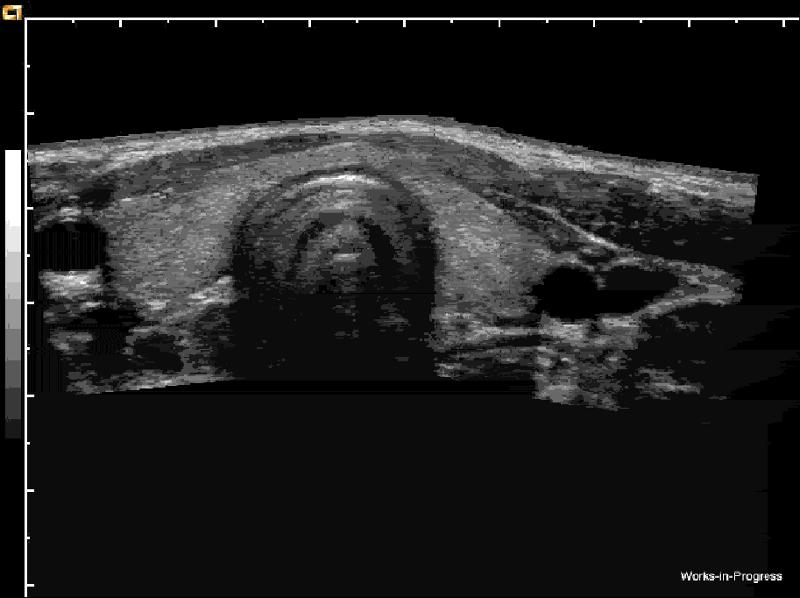

How should plaque be measured?

transverse measurement

lumen vs true lumen

Why is plaque measured in transverse?

Longitudinal estimation of stenosis from B-mode image is usually unreliable, use transverse image.

*This minor plaque can be made to appear more or less stenotic in longitudinal view